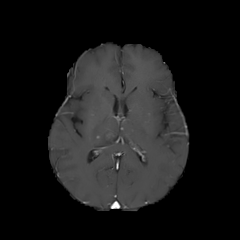

Objectives: This work aims to explore the impact of multicenter data heterogeneity on deep learning brain metastases (BM) autosegmentation performance, and assess the efficacy of an incremental transfer learning technique, namely learning without forgetting (LWF), to improve model generalizability without sharing raw data. Materials and methods: A total of six BM datasets from University Hospital Erlangen (UKER), University Hospital Zurich (USZ), Stanford, UCSF, NYU and BraTS Challenge 2023 on BM segmentation were used for this evaluation. First, the multicenter performance of a convolutional neural network (DeepMedic) for BM autosegmentation was established for exclusive single-center training and for training on pooled data, respectively. Subsequently bilateral collaboration was evaluated, where a UKER pretrained model is shared to another center for further training using transfer learning (TL) either with or without LWF. Results: For single-center training, average F1 scores of BM detection range from 0.625 (NYU) to 0.876 (UKER) on respective single-center test data. Mixed multicenter training notably improves F1 scores at Stanford and NYU, with negligible improvement at other centers. When the UKER pretrained model is applied to USZ, LWF achieves a higher average F1 score (0.839) than naive TL (0.570) and single-center training (0.688) on combined UKER and USZ test data. Naive TL improves sensitivity and contouring accuracy, but compromises precision. Conversely, LWF demonstrates commendable sensitivity, precision and contouring accuracy. When applied to Stanford, similar performance was observed. Conclusion: Data heterogeneity results in varying performance in BM autosegmentation, posing challenges to model generalizability. LWF is a promising approach to peer-to-peer privacy-preserving model training.